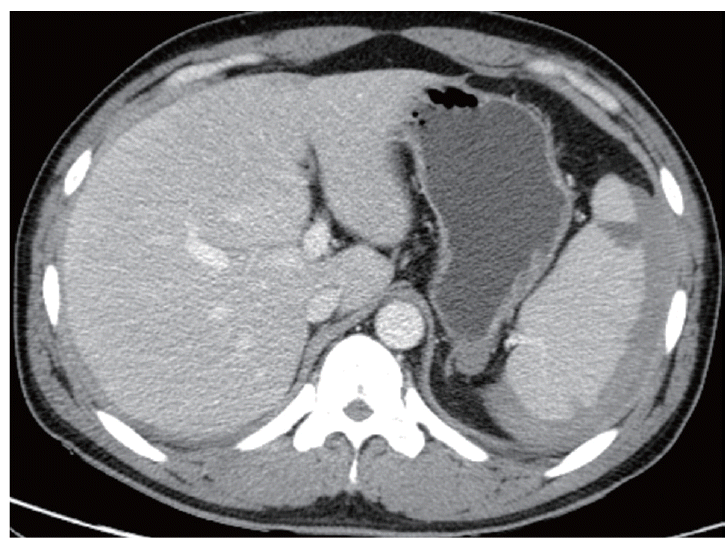

A follow-up CT was performed 5 days after the coil embolization. At this time, a reduced splenic subcapsular hematoma was observed. Several peripheral wedge-shaped low attenuated lesions were also found in the spleen, suggesting splenic infarction resulting from the coil embolization (Fig. 5). Hemoglobin levels were normalized (13.9 g/dl). After discharge, the patient has been closely followed-up at the Outpatient Department of Inha University Hospital. No other complications have developed.

Fig. 5.

Follow-up CT was performed 5 days after the coil embolization. The extent of the splenic subcapsular hematoma was decreased and splenic infarction developed.

kjp-53-2-215f5.gif